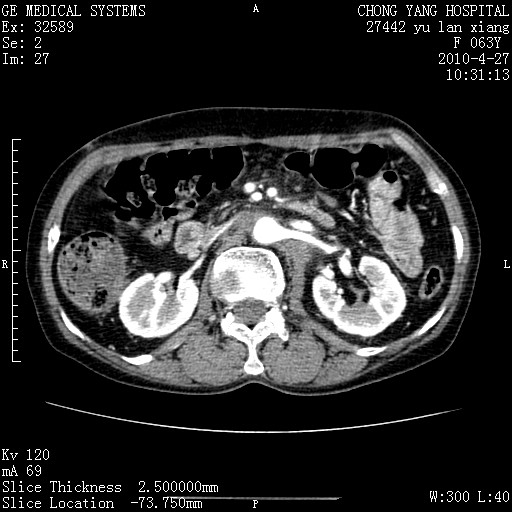

标题: CT26066:F63Y 上腹正中压痛半月,CA199:7400u/ml,MR示胰腺炎伴 [打印本页]

胰腺癌侵犯腹腔动脉干-分支、胃壁、左侧膈肌伴胰周及腹膜后淋巴结转移、胆囊切除术后。

胰腺癌侵犯腹腔动脉干-分支、胃壁、左侧膈肌伴胰周及腹膜后淋巴结转移、胆囊未显影。